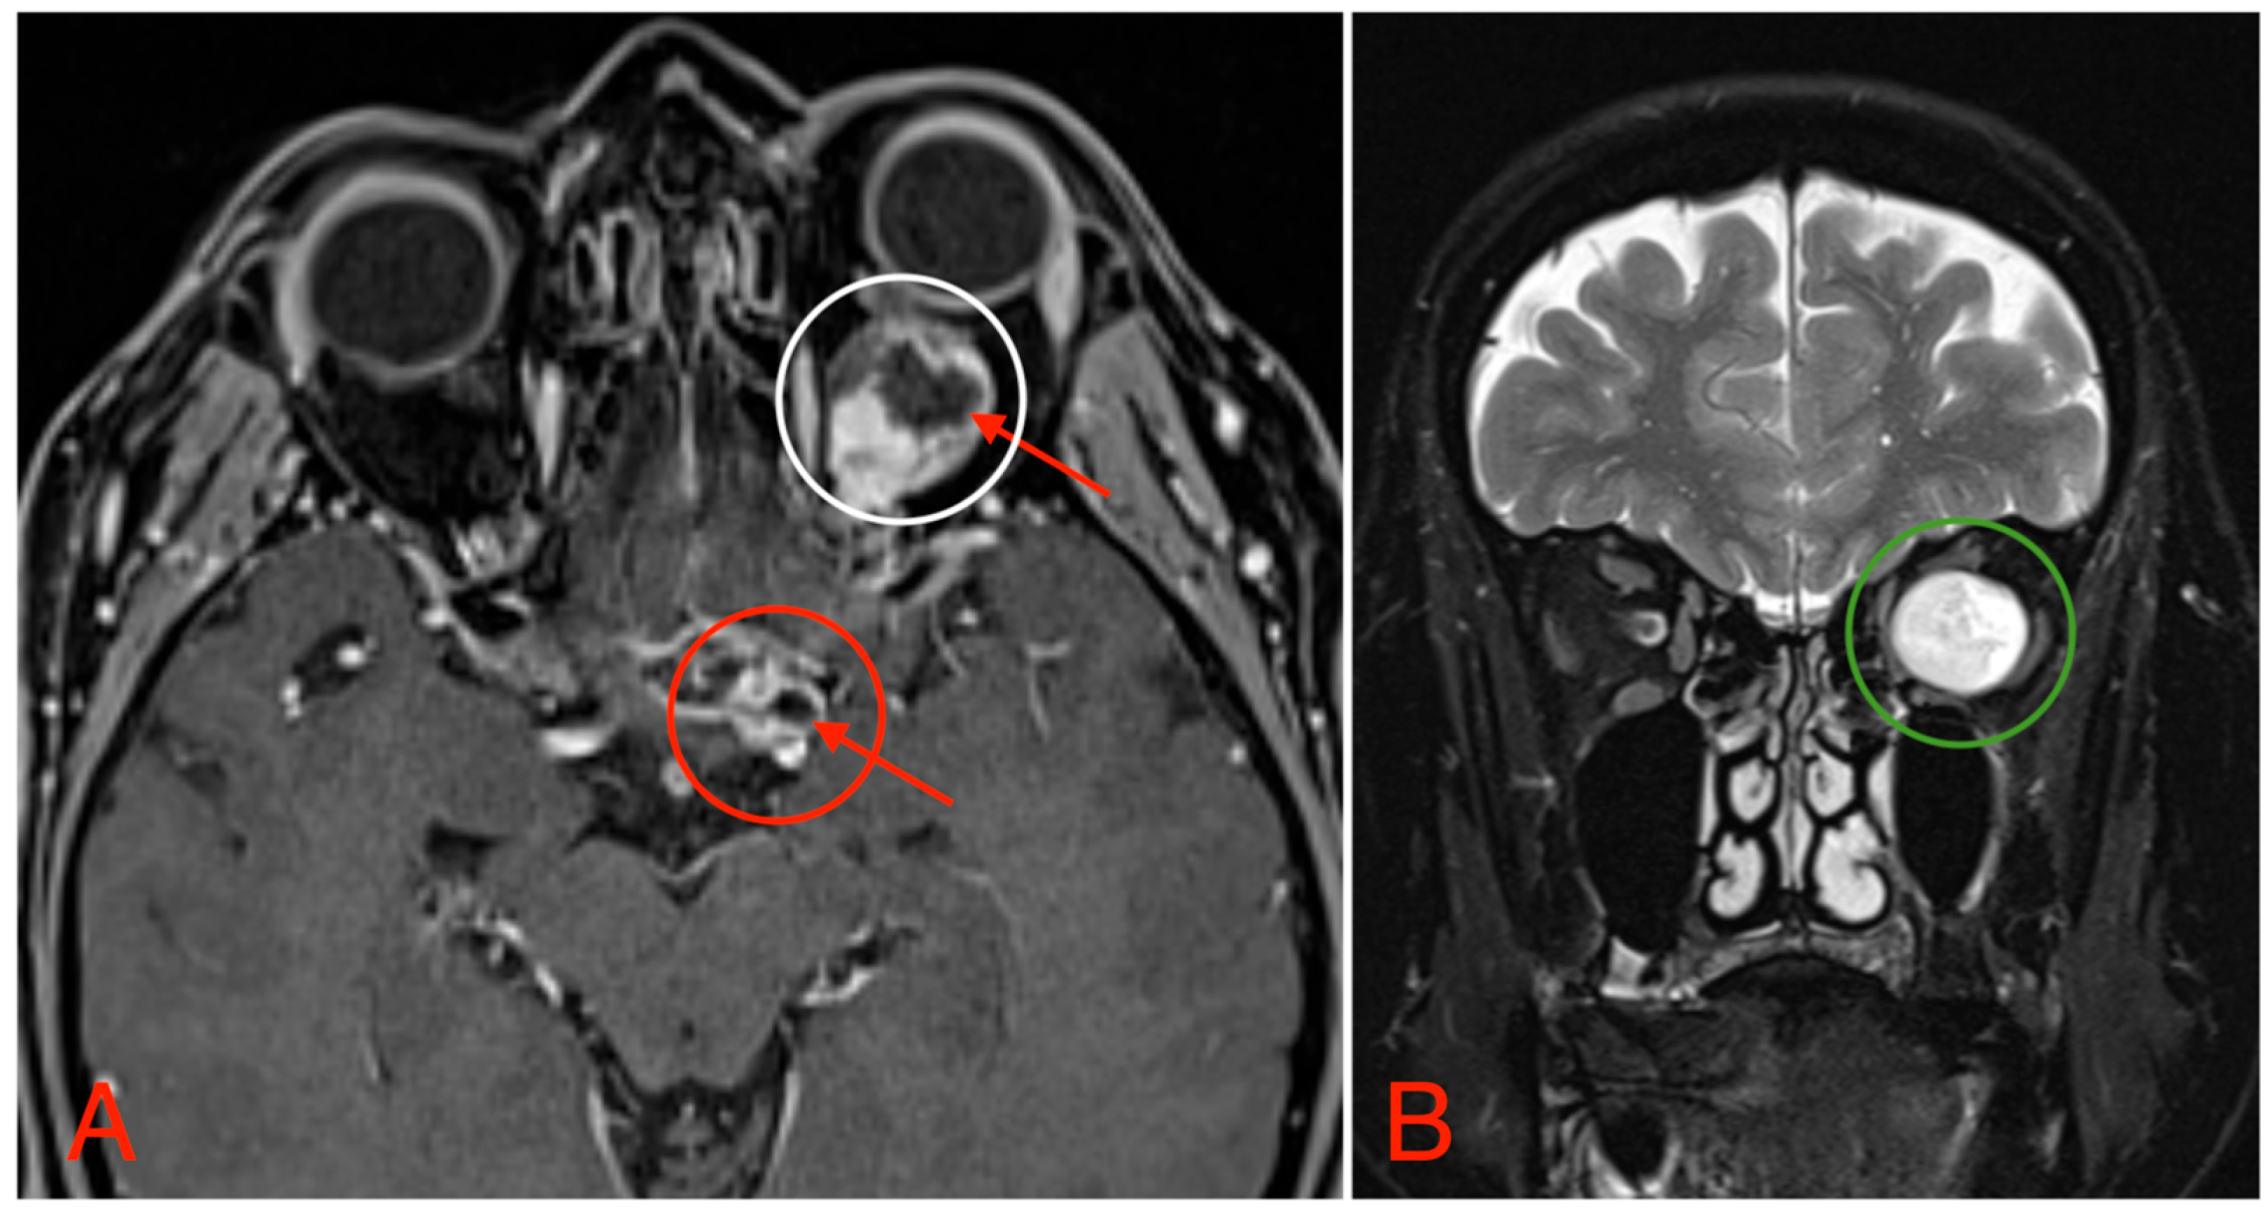

The CT scan revealed a pathological mass in the intraconal space, ~1.5 cm × 2.5 cm × 1.5 cm, which occupied most of the orbit. Noticeable thinning and depression of the rectus muscles of the eye were also noted (Figure 3). A cranial contrast enhanced MRI was conducted the following month, revealing an entirely altered optic nerve affecting the retrobulbar, prechiasmal, and optic chiasm level. A pathological, smoothly contoured mass with cystic changes was described and measured about 5.2 cm × 2.0 cm × 1.9 cm. Greater peripheral contrast accumulation in the pathological tissue extended along the optic chiasm and relatively close to the frontal lobe’s straight gyrus. The pathological mass also extended relatively close to the A1 segment of the anterior cerebral artery and stretched in the direction of the pituitary gland. A lateral depression of the extraocular muscles was also noted (Figure 4). The contrast-enhancing component of the tumor on diffusion-weighted imaging (DWI) sequence showed a restricted diffusion at an apparent diffusion coefficient (ADC) value of 1500 × 10−6 mm2/s, with a b value of 1000 s/mm2. A high T2 signal intensity was also noted.

Figure 4. (A) MRI image, T1 VIBE fat-saturated post-gadolinium image sequence, axial plane, demonstrating an intraconal tumor which most likely originated from the optic nerve with intraconal and intracranial involvement, cystic changes (red arrows), and contrast enhancement (white circle). The intracranial compartment involves the optic chiasm with a mass effect on the surrounding structures and large blood vessels (red circle). (B) MRI image, T2 TSE Dixon sequence, coronal plane, showing both solid and cystic parts of the optic nerve tumor with a retrobulbar segment mass effect and extraocular muscle suppression (green circle).